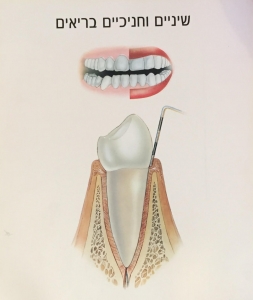

החיידקים המהווים את הגורם הראשוני למחלת חניכיים, מצטברים בדרך-כלל בגבול שבין השן לחניכיים, אזור שלא תמיד זוכה לתשומת לב מיוחדת בזמן הצחצוח.

כאשר החיידקים אינם מסולקים, אנחנו מבחינים ב- 2 שלבים עיקריים במחלות חניכיים:

ג'ינג'יביטיס – צורתה הקלה יותר של המחלה, הפוגעת בחניכיים בלבד.

החניכיים הופכות אדומות, נפוחות ומדממות בקלות.

תיתכן תחושת אי-נוחות קלה או כלל לא.

ג'ינג'יביטיס נגרמת לרוב כתוצאה מהיגיינה אוראלית לקויה.

בקבלת טיפול מתאים ובהמשך שמירה על היגיינה תקינה בבית, ניתן להחזיר את המצב לקדמותו ולהגיע להחלמה מלאה.